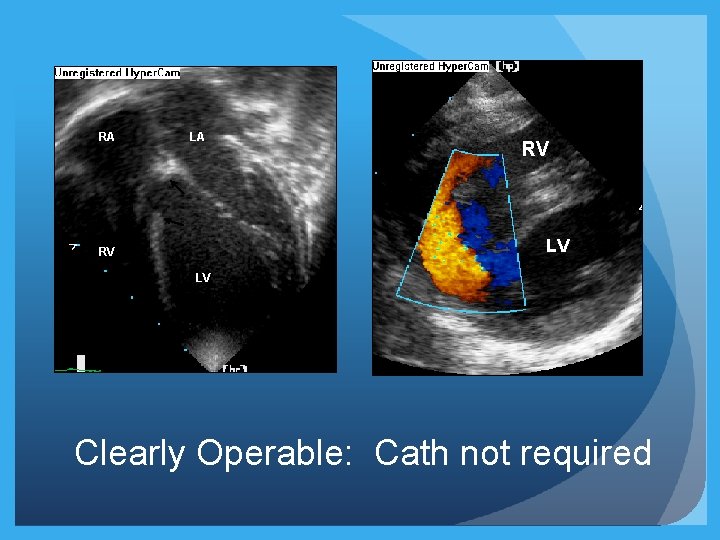

RA LA RV LV Clearly Operable: Cath not required